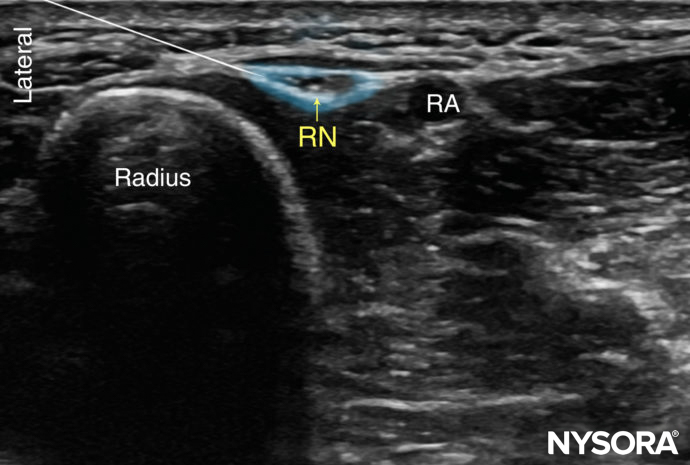

The superficial branch of the radial nerve divides into terminal branches at the level of the wrist; for this reason, ultrasonography is not very useful for nerve block placement guidance at the level of the wrist. A subcutaneous field nerve block around the area of the styloid process of the radius remains an easy method to perform an effective radial nerve block at the level of the wrist. However, ultrasonography can be used at the level of the elbow or in the mid-forearm. At this level, the nerve is identified as a thin hyperechoic structure lateral to the radial artery and superficial to the radius. The nerve exits the antebrachial fascia between the tendons of the brachioradialis and the extensor carpi radialis muscles (Figures 6 and 7).

FIGURE 6 (A) Cross-sectional anatomy of the distal forearm. (B) Sonoanatomy of the radial nerve (RN) at the forearm. RA, radial artery.

FIGURE 7. Sonoanatomy of the radial nerve (RN) at the level of the wrist. The superficial branch of the RN at the wrist is shown lateral to the radial artery (RA), and the approximate needle path to reach the branch of the radial nerve is shown with an approximate spread of local anesthetic (blue-shaded area) to anesthetize it.